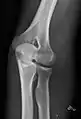

- Knee - AP and Lateral. Intra Condular projections on request

- Patella - Skyline projection

Right knee, anteroposterior

Right knee, lateral

Patella, (slightly skew) skyline